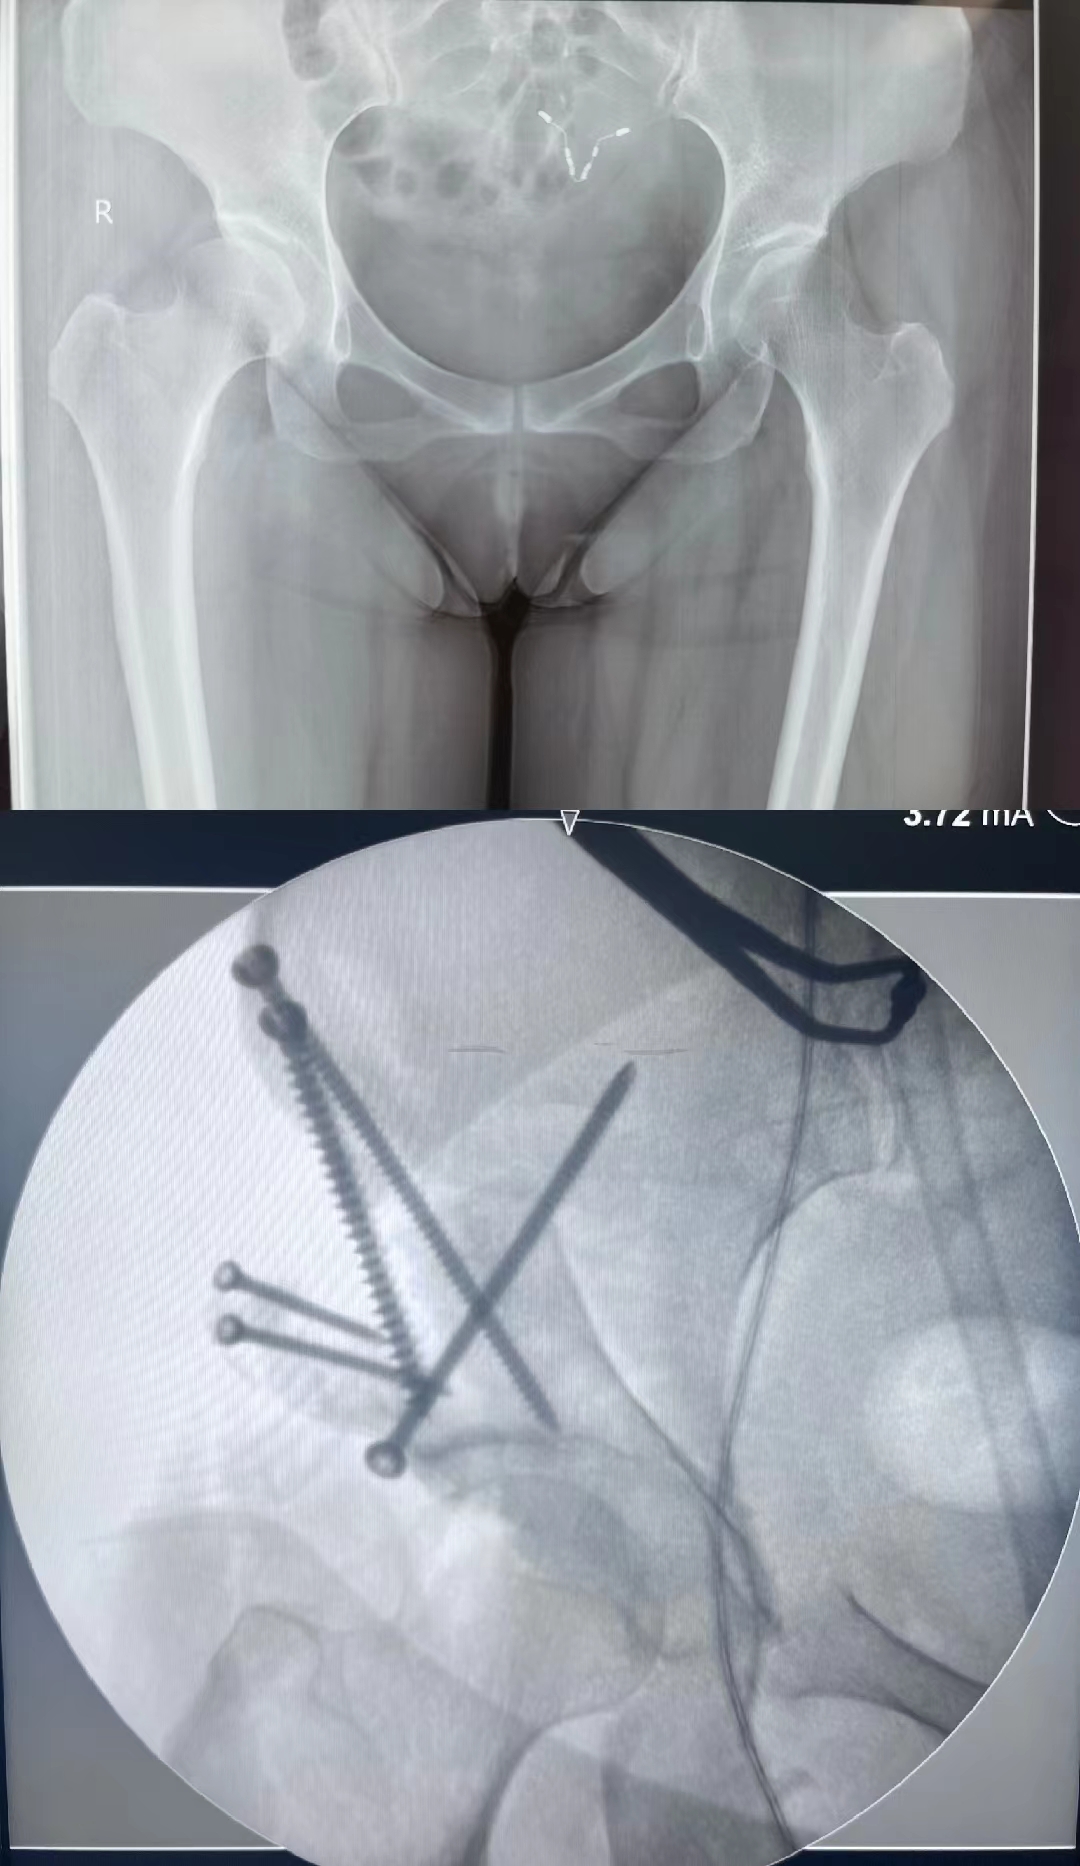

术前术后X线

近日,我院骨一科在党晓谦主任的带领下,时志斌主任医师、倪建龙副主任医师和冯萌博士团队成功为一位36岁女性髋关节发育不良(Developmental dysplasia of the hip,DDH)患者完成髋臼周围截骨(Periacetabular Osteotomy,PAO)手术,手术顺利,术后复查提示髋关节结构恢复正常,围术期无并发症发生,患者恢复良好。

骨一科多年来专注于关节外科及运动医学疾病的诊治,除了在复杂髋关节置换和翻修方面做了大量的工作之外,在保膝、保髋手术方面也积累了丰富的经验。继2015年首次开展髋关节镜镜下FAI手术,2020年首例髋关节外科脱位技术治疗陈旧股骨头骨折之后,本次成功开展的PAO术式,标志着我院已经全面掌握了保髋手术的三大关键性技术。本例患者入院后,党晓谦主任组织科室骨干力量,对患者病情进行反复研究和讨论,最终确定进行PAO手术,术前准备充分,应用三维CT和3D打印模型进行手术规划设计,在麻醉科手术室的配合下最终顺利完成手术,术后复查提示髋关节畸形得到完全纠正。本次手术的成功标志着我院在髋关节保护外科的发展中已经走在了西北的前列,为我院骨科影响力的扩大和学术地位的提高作出了贡献 。